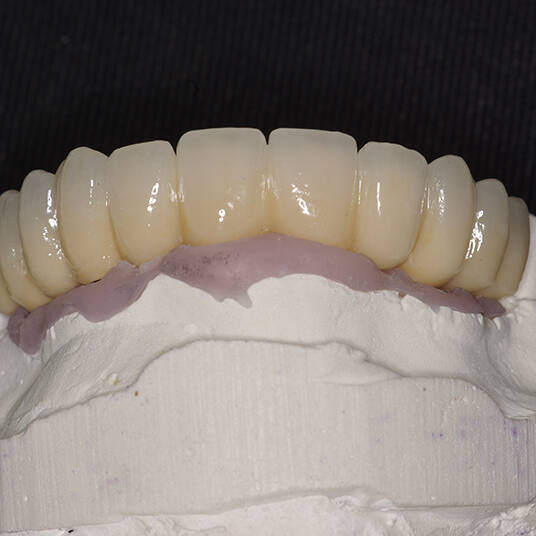

Tecnologia CAD CAM para Maior Precisão e Conforto

Utilizamos a tecnologia CAD CAM, um sistema avançado que possibilita a confecção precisa das próteses dentárias diretamente sobre os implantes. Esse método inovador garante um ajuste perfeito, um resultado estético superior e proporciona muito mais conforto e durabilidade. Com o CAD CAM, nossos pacientes contam com um processo mais rápido e previsível para alcançar o sorriso desejado.